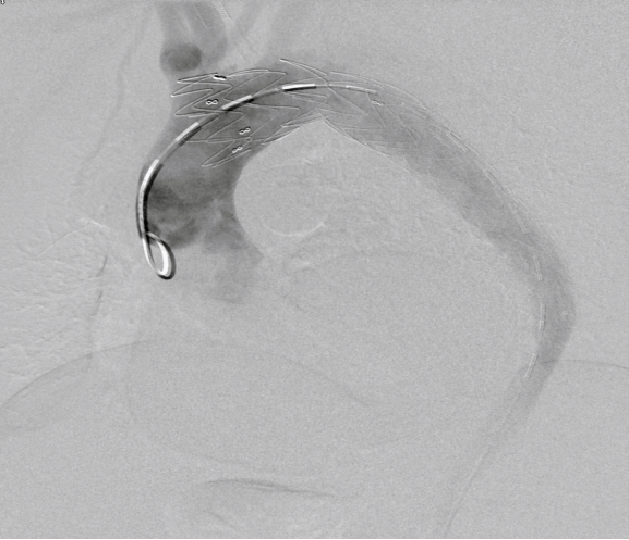

▎病例四

男, 49岁,急性夹层 。2018年11月TEVAR。一月后复查:RTAD 。 2019年1月双开窗。2019年4月2日 复查,结果良好。

RTAD治疗的“金标准”仍是开放修复。7例RTAD患者转心外科行全弓置换+支架象鼻,7例痊愈。腔内修复在Z0区再次TEVAR很可能再次RTAD。